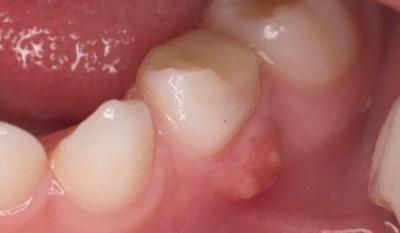

- Абсцесс — формирование гнойного очага воспаления вокруг корня зуба (или рядом с зубом) и в пародонтальных тканях. Десна при этом выглядит припухлой (чаще всего на воспалённом участке внутри десны просматривается небольшой шарик с гнойным содержимым). При прикосновении к шишке возникает острая боль (в т. ч. во время пережёвывания пищи). Болезнь развивается в результате размножения патогенных бактерий в ротовой полости, а также из-за мелких повреждений десны, стрессов и переохлаждения организма.

- Шишка на десне с гноем часто выступает симптомом абсцесса, периостита, эпулиса, челюстных опухолей (если произошло заражение через мягкие ткани).